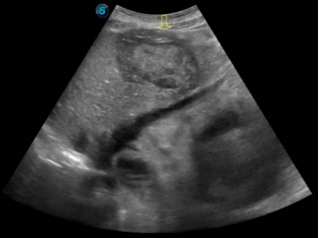

肝脏肿瘤,动脉期高增强,延迟期造影剂消退,造影考虑肝癌